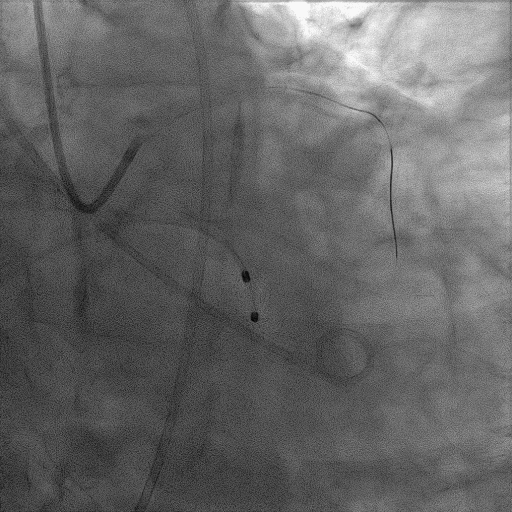

CAG:LAD近中段弥漫钙化,近段80%狭窄,中段90%狭窄,D190%狭窄,中间支近段90%狭窄,右冠近中段弥漫病变,最重狭窄50%。考虑患者胸痛症状可能为冠心病+AS共同作用,以及患者冠脉病变钙化严重,予以旋磨+PCI+TAVR一站式处理。

于中间支植入2.5*18mm支架

1.5mm旋磨头以16万RPM旋磨三次

3.0*15mm球囊后扩张

3.0*15mm球囊预处理LAD近段病变

复查冠脉造影结果满意

造影提示微少量返流,压力监测提示主动脉瓣压差7mmHg